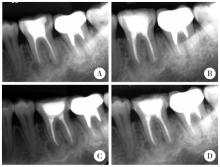

Figure 2

CBCT images of the patient at initial presentation Three radiographic stages of COD concurrently shown in multifocal lesions across six mandibular molars: osteolytic stage (38/46/48), cementoblastic stage (36/37), mature stage (47). The red arrow indicates the COD lesion. COD, cemento-osseous dysplasia; CBCT, cone beam computed tomographic."